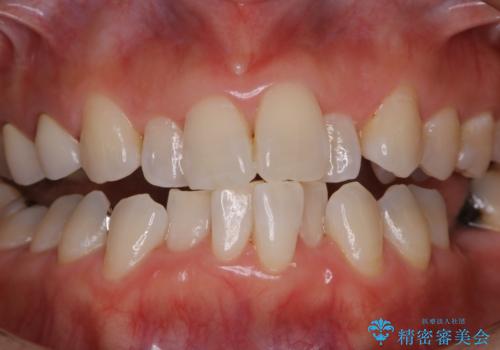

矯正治療の開始前にPMTCで汚れの除去

- これから矯正治療が開始される方です。装置の作成前にクリーニングを希望とのことでした。PMTC30分コースを行いました。

プラーク(細菌の塊)や歯石がたまると歯の表面はザラつきいてきます。そのザラつきは歯周病や虫歯菌の棲家となります。そのまま放置すると、歯肉が腫れてきたり、歯肉から出血したり、口臭が強くでたりします。とくに歯肉の境目は、歯磨きで汚れを除去することが難しく、プラーク(細菌の塊)や歯石が溜まりやすい場所です。

歯並が、がたついている場合はなおさら汚れが溜まりやすいです。矯正治療前や定期的にPMTCをすることで、矯正治療中の歯肉トラブルを防ぐことにつながります。